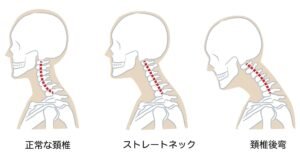

Изправена шийна лордоза – симптоми и лечение

Изправената шийна лордоза е състояние, при което естествената извивка на шийната част на гръбначния стълб се намалява или изправя. Нормално шийните прешлени ...